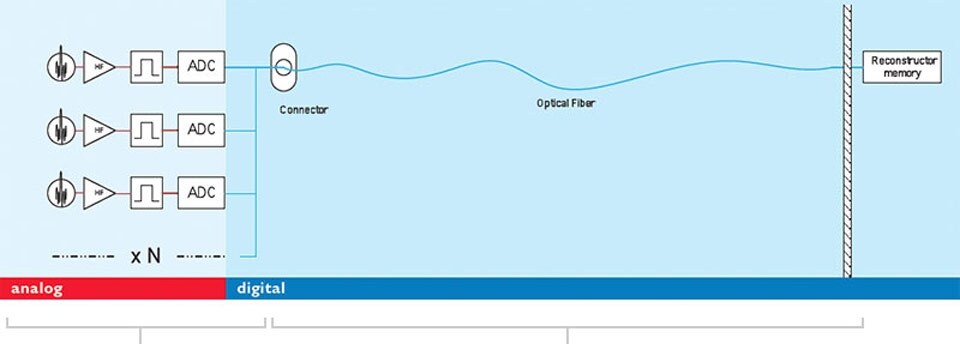

The dStream architecture uses a DirectDigital RF sampling method for digitization: the MRI signal is sampled directly, without conversion to DC. This technique avoids all intermediate analog stages for down-conversion of the signal between the coil element and the analog to digital converter (ADC).

The overall result is a simplified receiving architecture, with few components, low power consumption, high SNR and dynamic range, and enhanced signal and phase stability.

Digitization takes place in the coil itself. ADC electronics have been miniaturized and placed within the coil.

One fiber-optic cable for any number of RF channels replaces multiple coaxial cables and retains image quality. The number of RF channels is no longer a system specification.

dStream architecture

A visual explanation of dStream architecture.